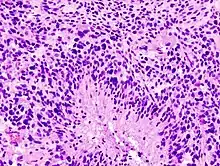

Les glioblastomes multiformes sont caractérisés par la présence de petites zones de tissu nécrosé entourées de cellules hautement anaplasiques. Cette caractéristique différencie la tumeur des astrocytomes de grade 3, qui ne possèdent pas ces zones de tissu nécrosé. Bien que le glioblastome multiforme puisse être issu d'astrocytomes de grades inférieurs, des autopsies post-mortem ont révélé que la plupart des glioblastomes multiformes ne sont pas causés par des lésions cérébrales antérieures.